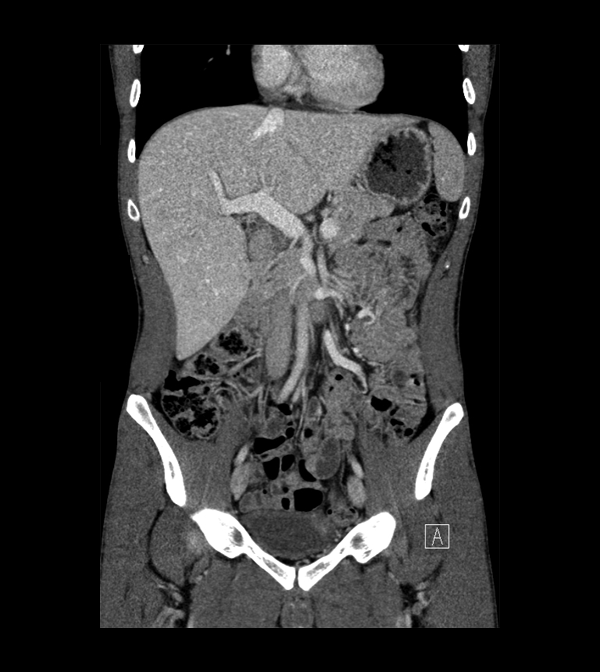

Body

Covers abdominal CT anatomy.